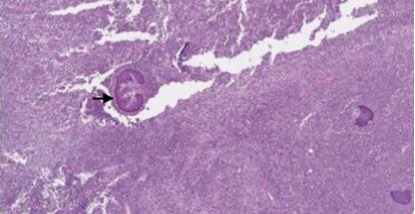

Notably, sulphur granules with actinomycotic colonies, filaments and club shaped structure (Speldore-Hoeppli reaction) were identified along within the abscess cavity [Figure 8, 9, 10]. The previously identified myofibroblasts on biopsy were attributed to reactive fibroblasts surrounding the abscess. Immunohistochemistry showed positivity for Ki-67 in 29.1% of cells and a few scattered IgG4-positive cells. ALK (5A4) and MUC-4 stains were negative.

FIGURE 9: Sulphur granule Sulphur granule (black arrow) shown is composed of masses of gram-positive bacteria with branching filaments and eosinophilic amorphous material with club shaped configuration surrounding the granule (Splendore-Hoeppli reaction).

FIGURE 10: Sulphur granule Magnified view of sulphur granule and Splendore- Hoeppli reaction

PAS staining revealed filamentous structures  consistent with Actinomyces, and Gram stain confirmed the presence of gram-positive branching bacteria. Based on the histopathological findings with identification of Actinomyces colonies and supportive special stains, the diagnosis of Actinomycosis of the left thigh muscle was established. The patient received appropriate antibiotic therapy for Actinomycosis. Long-term follow up remained uneventful with no recurrence or complication